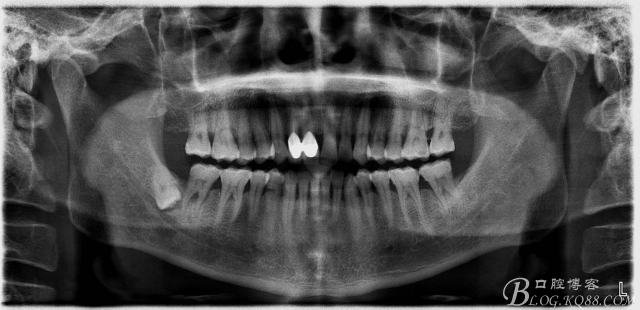

一、術前全景片影像:

48未萌出,47遠中可探及深約7mm的牙周袋。頰側47、48之間牙齦紅腫,有少量血性滲出。X線根尖片顯示:48牙冠反轉倒置,47遠中牙槽骨吸收明顯。CBCT顯示:48牙冠近中面位于下頜管內。